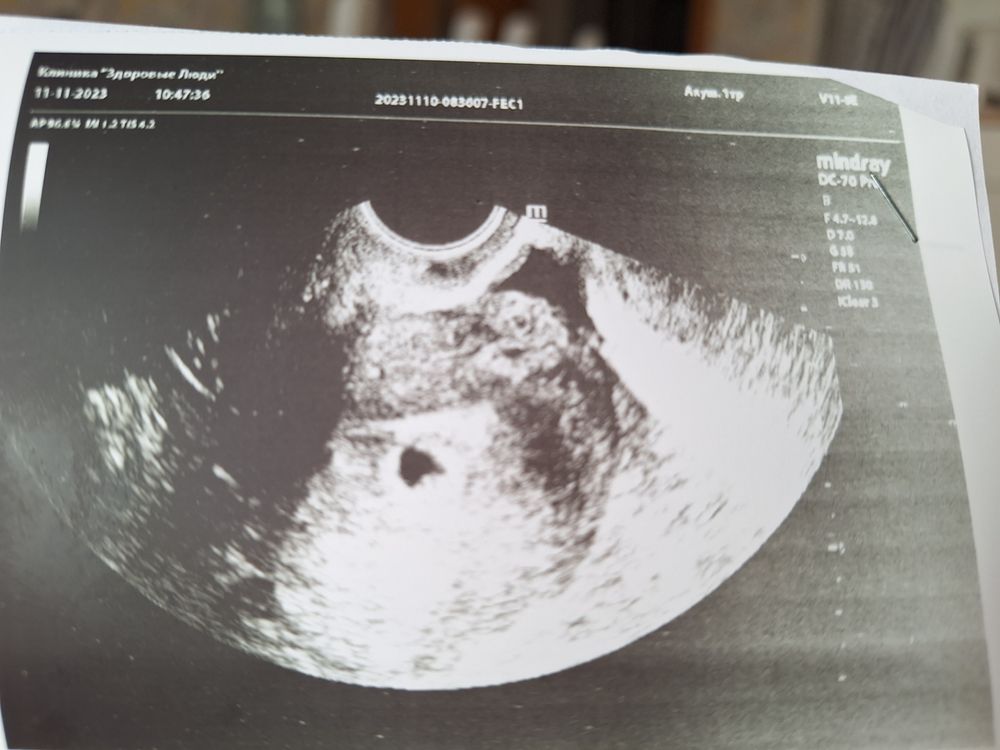

Первое узи 22дпо🥰

Хгч сегодня 4752 , пока эмбриона не видно маленький срок , через 2 недели повторное узи :)